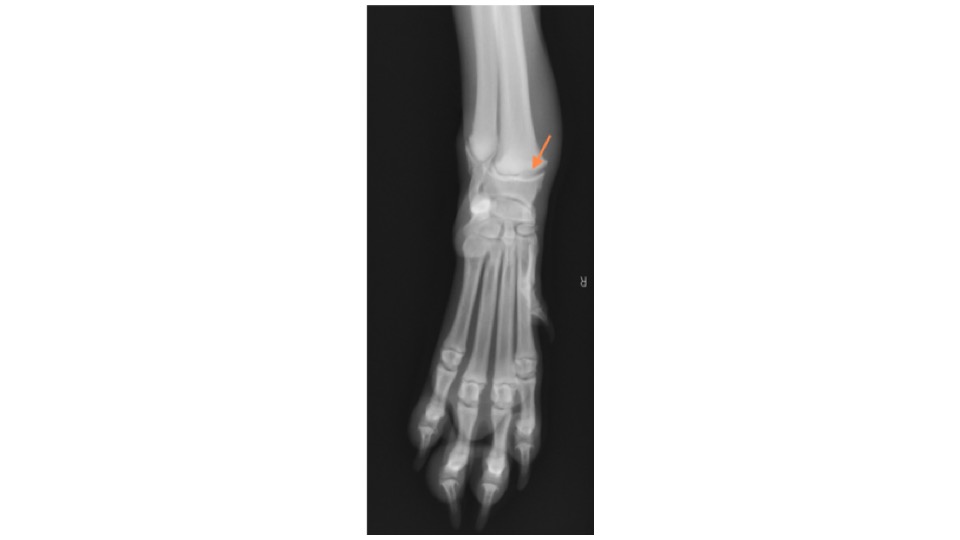

レントゲン検査を行ったところ、右手根骨のⅠ型成長板骨折が認められました。

→の部分が骨折部位になります。

この画像の曲線が、正常な成長板です。下の画像と比較してみると、わかりにくいですが骨折線が認められます。

成長板骨折は1方向だけのレントゲン画像では診断が難しいため、必ず2方向(横、正面)からの撮影を行います。